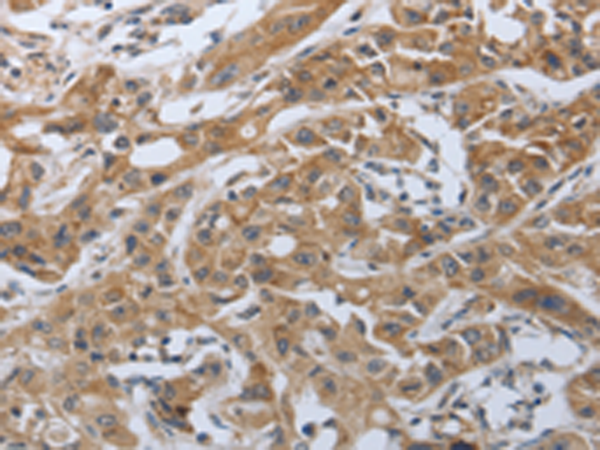

分类: 科研抗体货号: P04437别名: 42A, 18A2, CAPL, FSP1, MTS1, P9KA, PEL98应用: IHC反应种属: Human